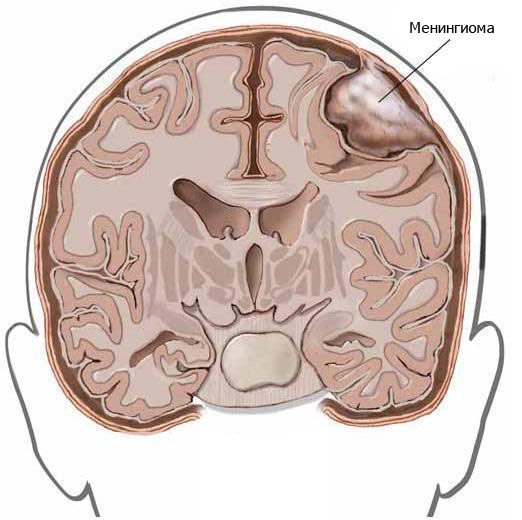

- менингиома;

- Менингиома: особенности диагностики и лечения